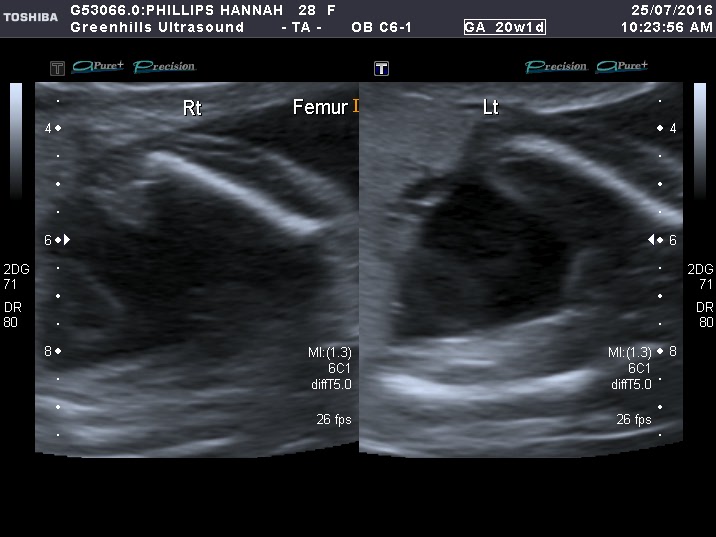

Last is between femurs at 20 weeks.